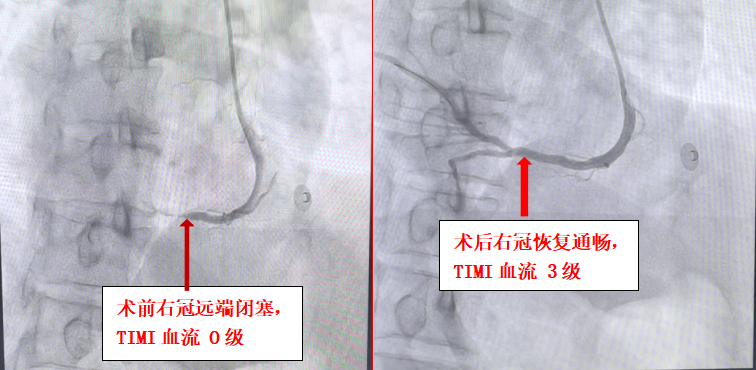

術中造影證實,患者供血心臟下壁的右冠狀動脈中遠段完全閉塞,TIMI血流0級,這正是此次心梗的“元兇”。在X光影像的引導下,手術團隊屏氣凝神,小心翼翼地操控著導絲,如同在鏡面中倒車,精準地通過閉塞段。面對閉塞處的高血栓負荷,團隊果斷采取冠脈內溶栓,待血栓負荷減輕后,順利植入支架。當造影劑再次通過血管,原本堵塞的血管瞬間恢復暢通,患者胸痛癥狀立即緩解,生命體征逐漸趨于平穩(wěn),手術成功了!術后患者被轉入心內科二區(qū)CCU病房進一步觀察,目前恢復情況良好。